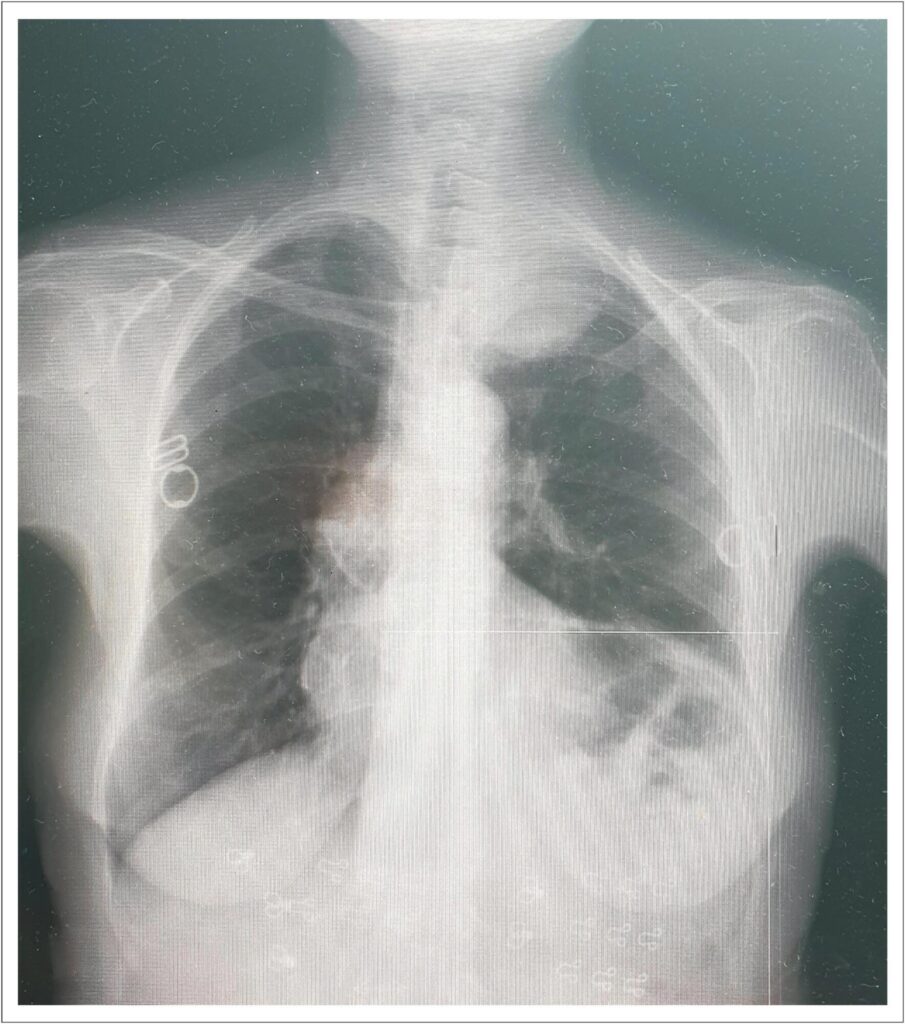

Aneurismas da artéria subclávia são anomalias vasculares raras que apresentam riscos significativos, incluindo tromboembolismo, isquemia e ruptura. O presente relato de caso descreve uma paciente do sexo feminino de 71 anos de idade que apresentou isquemia no braço esquerdo, incluindo dor, dormência e fraqueza, causada por um aneurisma da artéria subclávia esquerda complicado por trombose distal. A imagem revelou um aneurisma de 65 × 55 mm com uma oclusão trombótica de 2,5 cm. O aneurisma foi tratado com uma abordagem endovascular, utilizando um plugue vascular implantado via acesso femoral. Isso foi precedido por tentativas frustradas de acessar a lesão pela abordagem radial devido à presença de oclusão trombótica e anatomia vascular complexa. Após o procedimento, a paciente apresentou alívio significativo dos sintomas, e a imagem de acompanhamento confirmou a trombose do saco aneurismático. Este caso destaca a eficácia das técnicas endovasculares no manejo de aneurismas complexos da artéria subclávia e enfatiza a importância de estratégias de tratamento individualizadas e acompanhamento rigoroso.